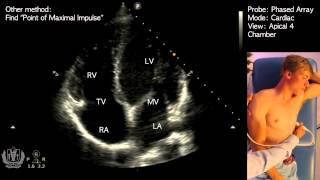

Apical 4 Chamber View on Transthoracic Echocardiography (Cardiac Ultrasound)

POCUS 101

40K

132,518

10 лет назад